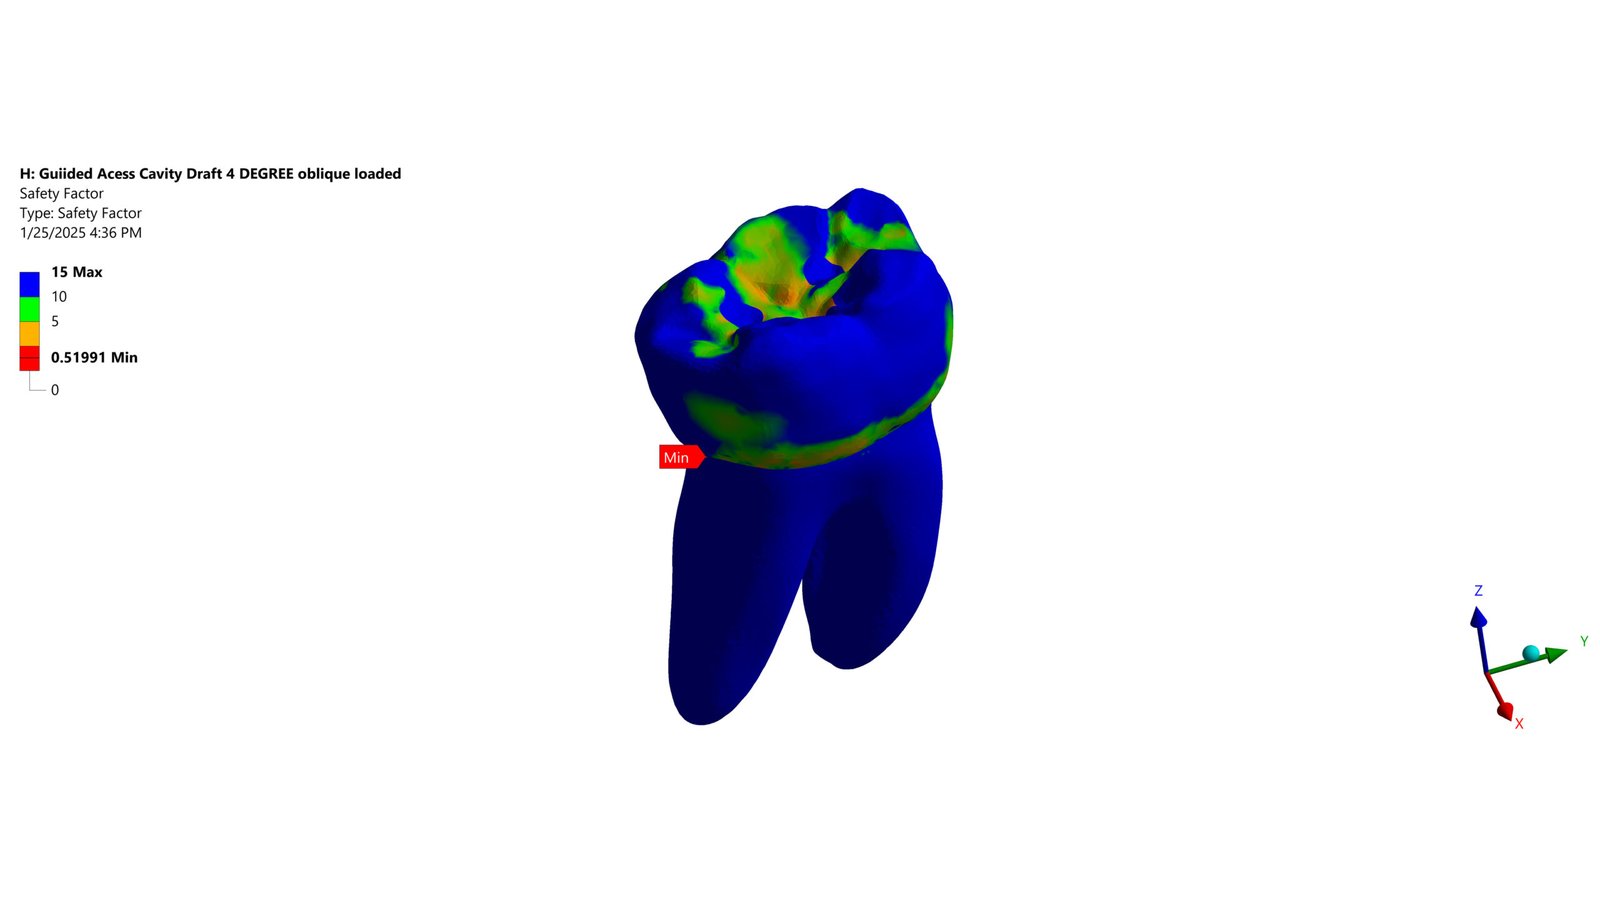

The Endodontic FEA section evaluates the biomechanical performance of root canal–treated teeth, endodontic tools, and reinforcement strategies. Through precise material characterization and micro-CT–based superimposition, we assess fracture risk, stress pathways, and instrument fatigue under various clinical scenarios. These simulations guide the selection of safer instrumentation techniques and restorative strategies. Our goal is to enhance predictability and reduce procedural complications.